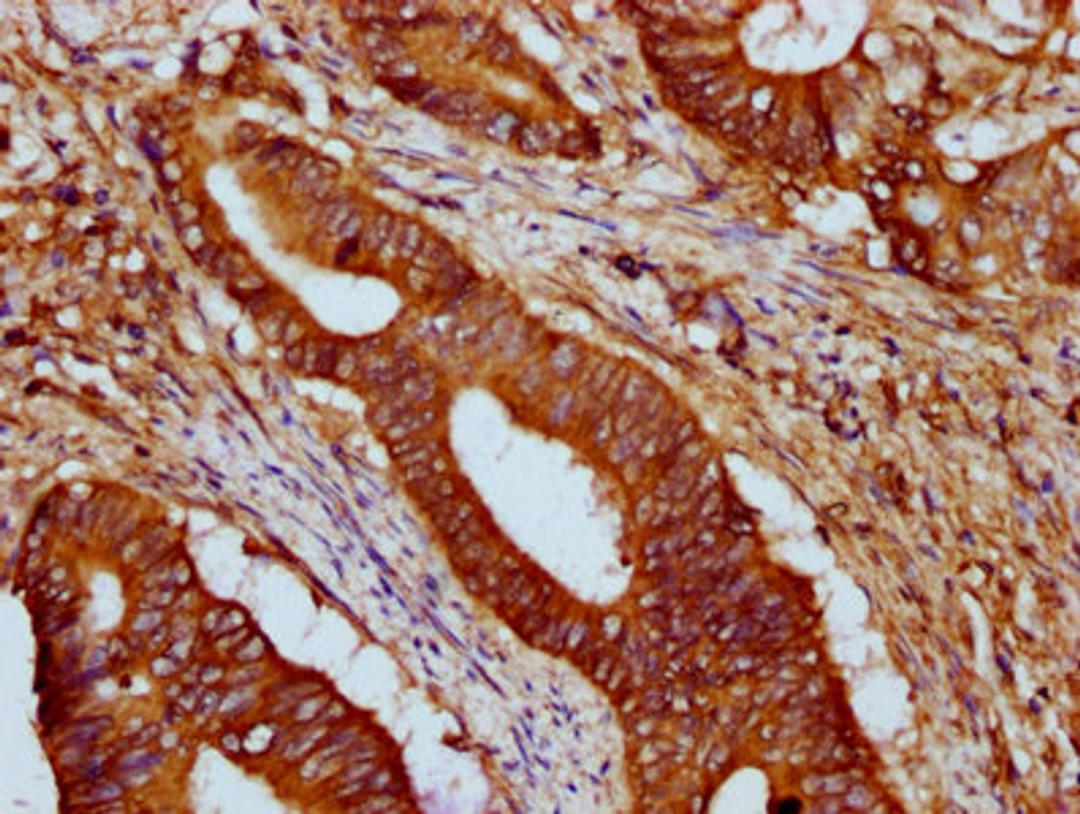

IHC image of CSB-PA010216LA01HU diluted at 1:500 and staining in paraffin-embedded human colon cancer performed on a Leica BondTM system. After dewaxing and hydration, antigen retrieval was mediated by high pressure in a citrate buffer (pH 6.0). Section was blocked with 10% normal goat serum 30min at RT. Then primary antibody (1% BSA) was incubated at 4°C overnight. The primary is detected by a biotinylated secondary antibody and visualized using an HRP conjugated SP system.